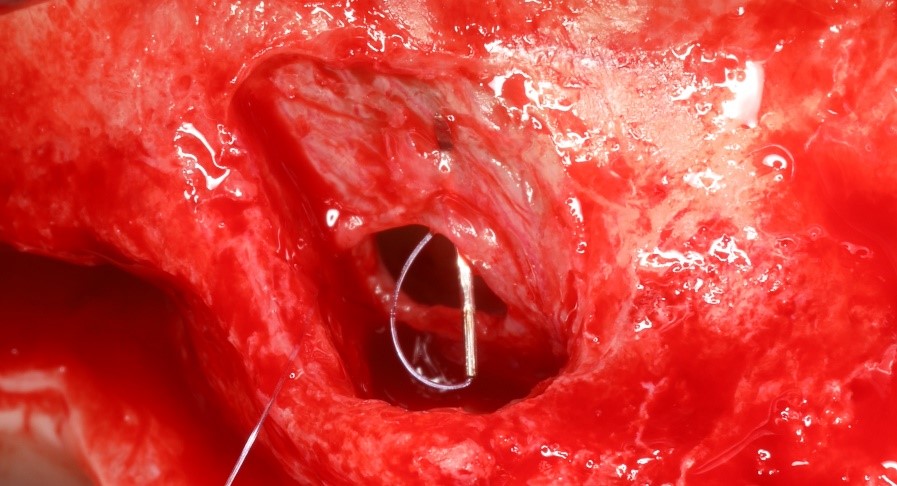

Dr Romain DOLIVEUX

La fermeture d’une perforation de la membrane sinusienne lors de la réalisation d’un sinuslift est incontournable.

La méthode de choix est la suture. Etant donnée la finesse du tissu, celle-ci ne peut être réalisée qu’avec un fil de diamètre réduit, résorbable et une aiguille adaptée.

Le Monosorb 7.0 monté d’une aguille 3/8 de 8mm de qualité est parfaitement adapté à ce geste fin et délicat.